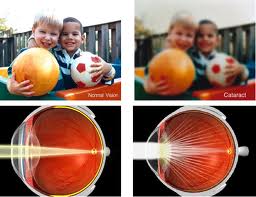

What is Cataract?

Opacification of normally transparent lens of human eye is known as Cataract. The opaque lens does not allow the light rays to pass to the retina so that clear image is not formed over the retina. The patient experiences painless decrease in vision. The objects appear blurred.

CATARACT